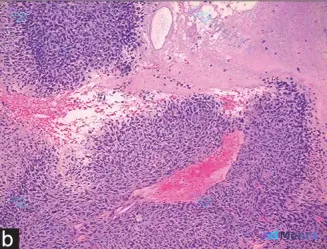

网上看到一份病理HE切片的描述和分析,有点意思,抛出来大家聊聊读片思路: > 显微镜下见: > 1. 细胞密集呈实性巢状/片状,圆形/卵圆形/梭形,核浆比显著增高,核大小基本一致(单调性),染色质深染,核仁不明显; > 2. 间质稀少,但血管极丰富,可见扩张充血的血管穿插于细胞团间,伴区域性出血;...

整理了一个青少年骨痛病例,资料给大家列一下,先来讨论一下最可能的诊断方向: 基本情况:14岁男性,右腿疼痛1个月,母亲自行给予夜间酮咯酸口服,疼痛无改善。 体格检查:右侧股骨中部局限性压痛。 影像学:右下肢X线提示股骨骨干及周围皮质可见数个溶解性病变,周围覆盖多层新骨形成。 活检病理:提示小圆形蓝色...

病例资料整理 基本信息 - 性别:男 - 年龄:9 岁 - 主诉:小腿出现肿块 - 既往史:无外伤史,其他方面健康 影像表现(图 A) - 左侧胫骨中段骨质破坏,骨皮质连续性中断。 - 浸润性表现,边缘不规则,过渡区宽。 - 可见骨膜反应,呈不规则层状或放射状(日光射线征)。 - 骨髓腔结构破坏,密...

整理了一张很有代表性的病理HE染色片(X400),结合读片分析梳理了一下鉴别思路,和大家分享。 --- 一、先看影像核心特征 1. 整体架构:高细胞密度病变,弥漫性密集分布,无明确腺体或上皮排列,属于经典的「小圆蓝细胞肿瘤」(SRBCT)形态;背景是少量纤维结缔组织,特别干净,几乎没有炎细胞浸润。...